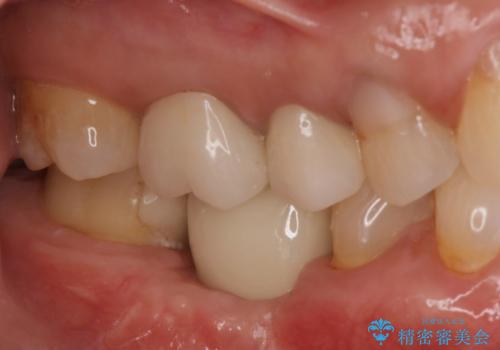

『インプラント』主訴:歯を入れたい

二回の手術を終えて最終的な被せ物が入るまで6〜8ヶ月かかると思います。

歯のなかったところをインプラント治療を行うことによってまた噛める喜びを感じていただけて良かったと思っております。